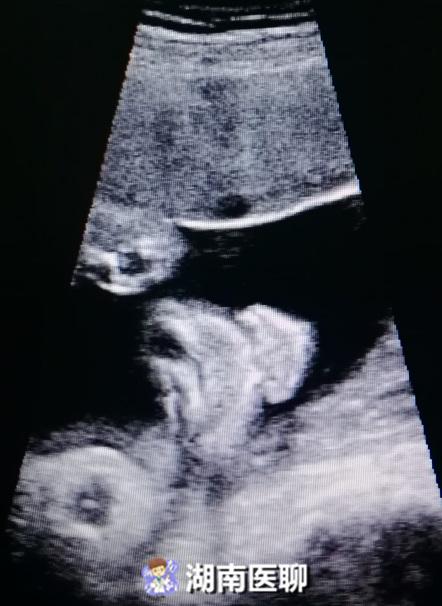

同理,胎儿二维彩超就是通过胎儿的某个平面来观察胎儿的结构,当医生不断移动探头的时候,所观察到的平面也随之不断的切换,

但由于超声波是通过探头连续发射的,所有平面的切换自然也是一个连续的过程,当把图像冻结也就是定住后,就形成了一副副二维平面图,如下: